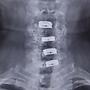

[請益] 頸椎開刀半年後手麻(內有x光)

[ Doctor-Info ]

6

留言, 推噓總分:

+5

作者: biottn - 發表於

2023/04/13 21:13

(3年前)